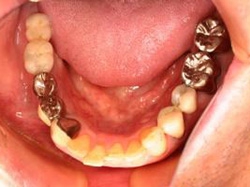

片側2歯欠損 主訴-入れ歯を使ってみたが違和感強くてダメ。固定のものにしたい。術前下顎口腔内(鏡像)

術前(下顎粘膜面、鏡像)